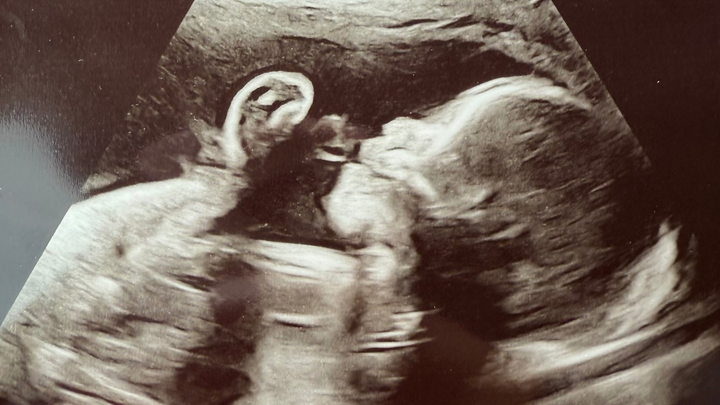

She and her husband, Edgar, are expecting their first child, sweet baby girl, Valentina. She is already so deeply loved, and we are trusting for strength, healing, and provision every step of the way. I created this GoFundMe to support them as they prepare for the medical care, surgeries, and unknowns ahead.

Valentina has been diagnosed with several complex congenital heart and organ conditions. She has Hypoplastic Right Heart Syndrome (HRHS), meaning the right side of her heart is underdeveloped. She also has Double Outlet Right Ventricle (DORV), where both major arteries come from the right side of her heart instead of being properly separated.

In addition, Valentina has Pulmonary Stenosis (PS), which means the pathway to her lungs is very narrow, making it harder for blood to flow properly.

She has also been diagnosed with heterotaxy syndrome, a condition that affects how her organs are arranged. Her stomach is on the right side, her liver sits in the middle, her intestines are rotated, and she does not have a spleen, which can affect her immune system.

Because of these conditions, Valentina will need at least two major heart surgeries, one around 3 months old and another around 3 years old, to help correct the “plumbing” of her heart and improve how it functions.

Immediately after birth, she will be transferred to the pediatric cardiac care unit at Children’s Hospital. There, doctors will perform genetic testing, an MRI, and evaluate whether her pulmonary veins are properly connected to her heart. Depending on what they find, she may need emergency surgery right after birth.